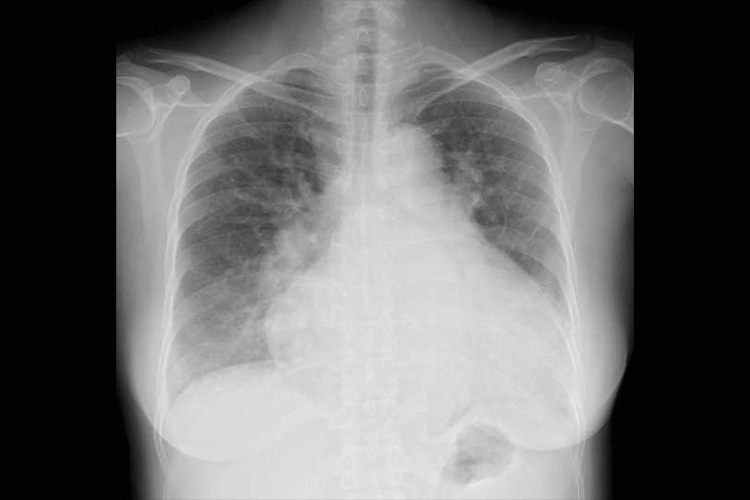

①胸部レントゲン検査

胸部レントゲン検査のイメージ

左右の肺に挟まれた縦郭全体を確認します。大動脈が拡大したり蛇行していないか、石灰化していないか等を確認します。